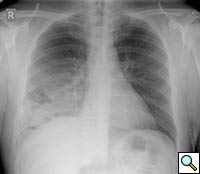

| Figure 1: Initial chest radiograph |

A previously healthy 43-year-old male presented with cough, fevers, and leukocytosis. A chest radiograph (Figure 1) revealed extensive consolidation in the right lower lung containing multiple cavities with air-fluid levels consistent with a necrotizing infection. A chest computed tomogram (Figure 2) showed an abscess cavity and consolidation in the right lower lobe with an aberrant blood supply from the descending aorta. This systemic blood supply was confirmed by subsequent 3D reconstruction (Figure 3). He was initially treated with IV antibiotics, resulting in normalization of his temperature and white blood cell count. He was then discharged home on a 3-week course of oral antibiotics. Three days prior to a planned surgical resection, he underwent angiographic localization of the feeding artery (Figure 4) and coil embolization (Figure 5).